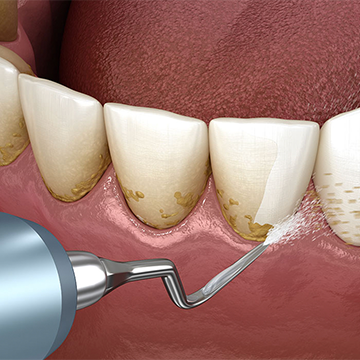

Periodontitis tedavisinde, patolojik süreci hızlandıran dişlerin yüzeyinde yapışık halde bulunan bakteri plağını ortadan kaldırmak ve optimum ağız hijyeni alışkanlıklarını oluşturmak esastır

Bu ilk aşamada, hastanın ağız hijyenine yeterince uyduğundan emin olmak çok önemlidir. Hastanın diş fırçası, diş ipi ve arayüz fırçası gibi kendinin kullandığı temizlik araçları ile erişemeyeceği bölgelerdeki diş taşı ve bakteri plağını ortadan kaldırmak çok önemlidir. Bazı vakalarda profesyonel tedaviye rağmen dokulardaki enfeksiyon devam edebilir, bu durumlarda tedaviye ek olarak antibiyotik tedavisi önerilir.

Bu ilk aşamadan birkaç hafta sonra hastanın periodontal sağlığı, hijyeni ve hastalığın ilerleyişi kontrol edilir. Periodontal cep (diş eti ve kemiği yok etme yeteneğine sahip bakterilerin bulunduğu boşluk), adı verilen dişeti ile alveolar kemik arasındaki boşluğun derinliğini kontrol etmek için sondalama yapılır.

Bu derinlik ne kadar fazla ise hastalık o kadar ilerlemiş durumdadır ki bu derinlik dokulardaki yıkım ile doğru orantılıdır Periodontal cep mevcudiyetinde dişeti kaldırılarak flap operasyonu yani dişeti ameliyatı yapılması gereklidir. Dişeti ameliyatı ile, dişeti altındaki istenilen bölgelere ulaşılır ve detaylı temizlik yapılabilir. Bu ameliyat ile doğrudan bir görüşe sahip olunur ve ilgili alanın tamamen temiz olduğundan emin olunmasını sağlar.